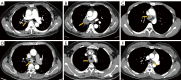

Figure 1

The preoperative CT scan images of the cases. (A) Patient 1 showed a 4 cm × 5 cm irregular mass in the RMB with hilar and mediastinal lymph node enlargement (yellow arrow); (B) patient 2 showed an 8 cm × 10 cm broccoli-like tumor in the bronchus intermedius involving the distal RMB (yellow arrow); (C) patient 3 showed a 3.0 cm irregular mass on the carina involving the orifice of the RMB with mediastinal lymph node enlargement; (D) patient 4 showed a 3.0 cm irregular mass with a rough and vascularized surface located in the carina. The proximal margin of the tumor was 1.2 cm above the carina, and the distal margins were 1 cm and 0.8 cm from the orifices of the LMB and RMB (yellow arrow); (E) patient 5 showed a longitudinal 3.5 cm irregular neoplasm involving the right and partial anterior wall of the thoracic trachea 2.5 cm from the carina (yellow arrow); (F) patient 6 showed an oval mass in the lower trachea measuring 4 cm longitudinally and involving the carina and the LMB orifice (yellow arrow). CT, computed tomography; RMB, right main bronchus; LMB, left main bronchus.